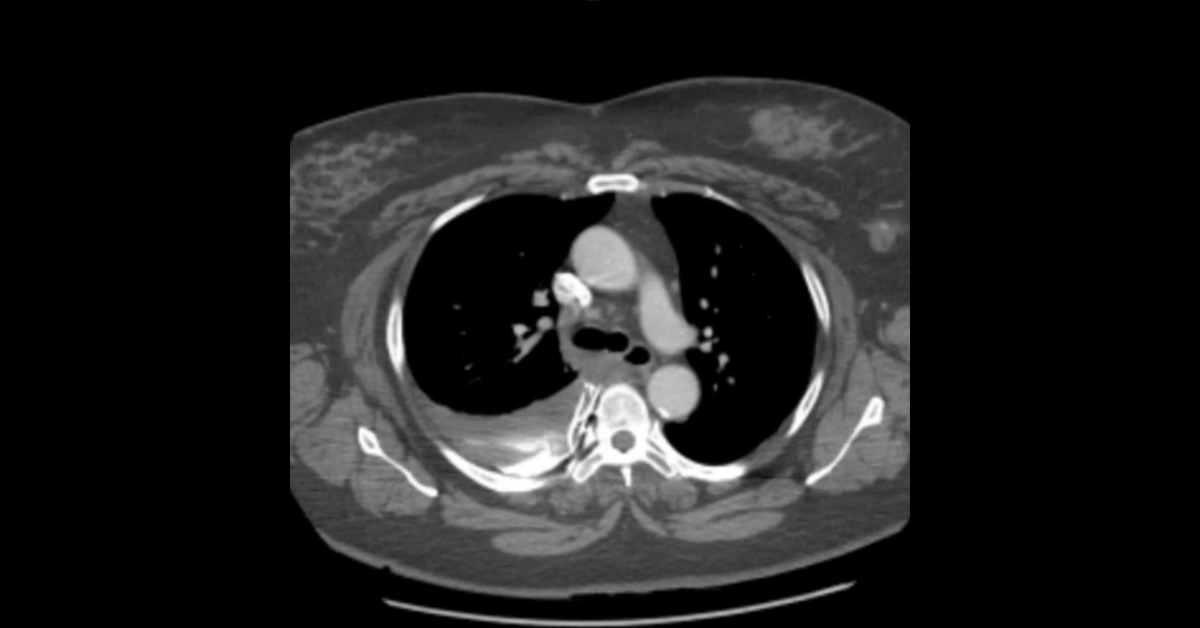

Course Overview

A collection of obstetric ultrasound studies presented in cine and screen shot formats, with initial presentation of each case enabling participants to render their own diagnoses followed by detailed discussion of each case.